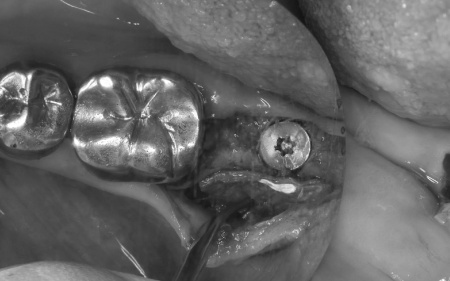

治療中

インプラント体と骨の結合を確認しました。